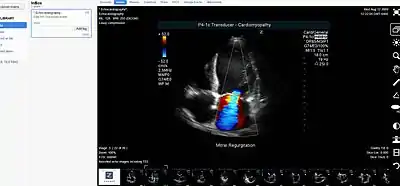

- Picture archiving and communication system (PACS) - A medical imaging technology that provides economical storage of, and convenient access to, images from multiple modalities within a facility.

- Medical imaging

- Radiology

- Picture Archiving & Communications System (PACS)